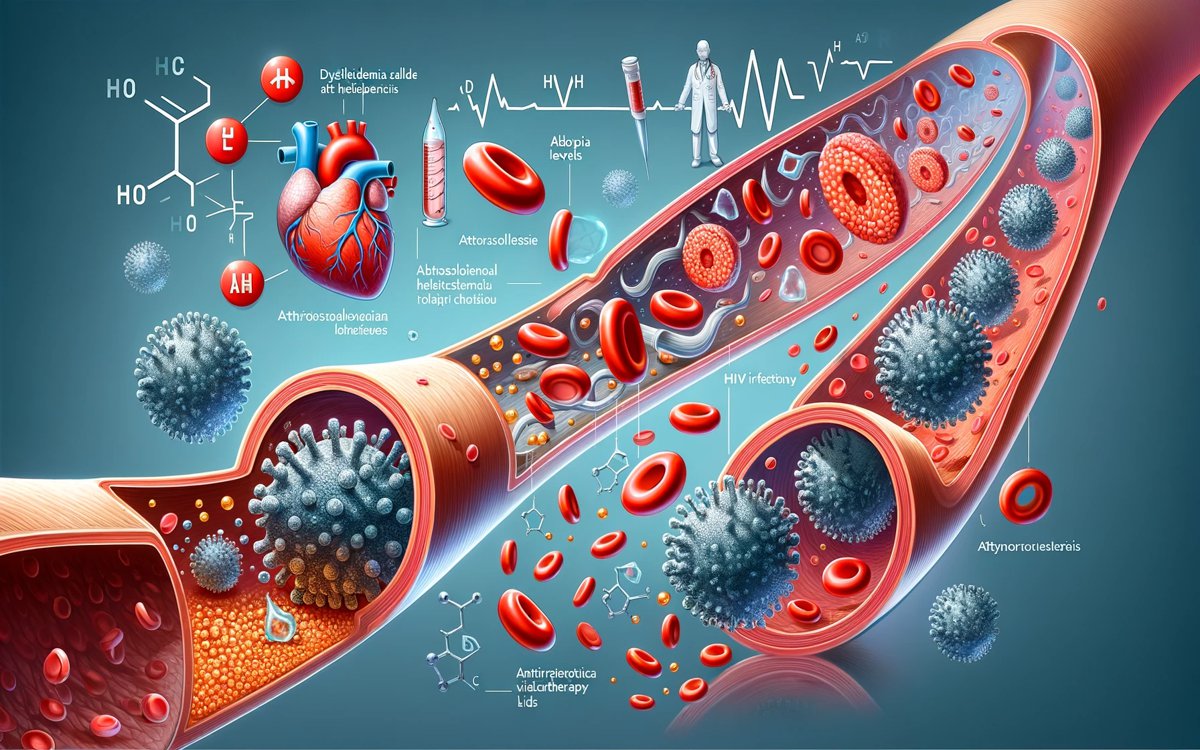

Изображения, связанные с атеросклерозом нижних конечностей и его лечением